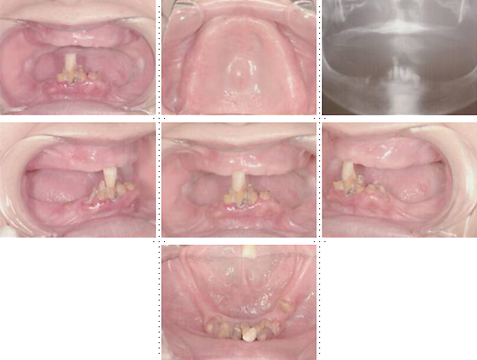

症例2

62才 女性

上顎は総義歯、下顎はブリッジと局部床義歯が装着。義歯は違和感があり、食事も不便を感じ、審美的にも人前にでるのが苦痛に感じていました。この状態を打破するためにも、「インプラント治療に自分の人生を賭けてみたい」という覚悟で来院されました。インプラント手術に対する恐怖心も強くお持ちでした。このような骨幅が狭いケースでは、X線撮影と共にCT撮影による画像診断とインプラント埋入シミュレーションが重要です。

下顎は両側犬歯を残し、他は抜歯。インプラント7本埋入。 上顎はインプラント8本埋入。 インプラント手術を受けられる患者さんは、前の晩眠れない程の不安感、恐怖心を持って来院されます。実際には麻酔注射は痛みを感じず、インプラント手術も痛みも無く、短時間(1本平均3分)で終わるという、当院独自のテクニックにより、2回目からのインプラント手術は気楽になるようです。 前歯は仮歯の段階で患者さん、歯科医、技工士の三者で、審美性・機能性の面から10回以上形態修正を繰り返し検討した後、上・下顎共に前歯・小臼歯はセラミック(MB)クラウン、大臼歯はゴールドクラウンを装着。ご本人とご家族の方にも、「アンチエイジングには、審美インプラント治療が一番効果あり」と大変喜んで頂きました。